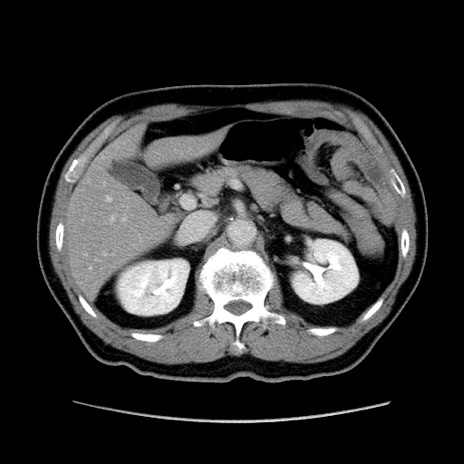

症例34(横断像)

【症例】60歳代 男性

【主訴】右鼠径部膨隆

【現病歴】1年程前より右鼠径部膨隆あり。自己にて還納可能だったため放置していた。3時間前より右鼠径部の脱出を認め、還納困難となり受診。

【身体所見】右鼠径部に小児頭大の膨隆あり。弾性硬であり、用手還納は困難。左鼠径部にも膨隆を認める。脱出はなし。